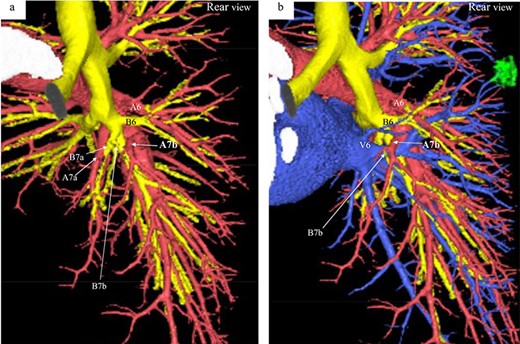

Three-dimensional CT angiography and bronchography images. (a) Rear-view CT angiography image of the PA and bronchi. (b) Rear-view CT image of the PA, PV, and bronchi. Reconstructed images of the pulmonary arteries (red), pulmonary veins (blue), bronchi (yellow) and tumor (green). A, pulmonary artery; B, bronchus; V, pulmonaryvein.

A 56-year-old man was referred to our department for a right lower ground-glass nodule (GGN). Computed tomography (CT) revealed a pure GGN measuring 12 mm in diameter in the S6 of the right lung (Fig. 1). A pathological diagnosis could not be determined via transbronchial tumor biopsy. Three months after the initial investigation, CT revealed that the GGN had not shrunk, and a highly differentiated adenocarcinoma was strongly suspected. No hilar or mediastinal lymph nodes, or other organ metastases were observed on positron emission tomography/CT, or contrast-enhanced magnetic resonance imaging of the brain. Preoperative 3D CT revealed an aberrant A7b branching from the basal pulmonary artery (PA) and running behind the V6 (Fig. 2). The A7a and A7b subsegmental pulmonary arteries were located on the ventral and dorsal sides of the basal vein, respectively. Because lung cancer was highly suspected, surgery was scheduled.